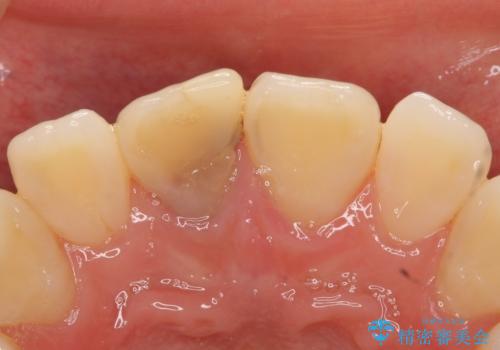

- 右上1番目の前歯の変色が気になるといらっしゃった方の症例です。

再根管治療後、オールセラミッククラウンによる補綴を行いました。